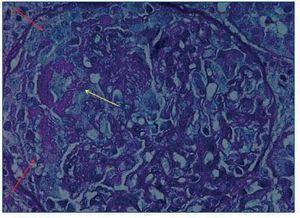

Cuatro días después del ingreso se le realizó una biopsia renal percutánea, en la que se observó una glomerulonefritis extracapilar (100% de semilunas), con colapso del ovillo glomerular, focos de necrosis fibrinoide, moderado infiltrado inflamatorio e incipiente fibrosis intersticial y atrofia tubular (figura 1). La inmunofluorescencia evidenció depósitos lineales de inmunoglobulina G (IgG) alrededor de la membrana basal glomerular.

Figura 1. Glomerulonefritis extracapilar (flechas rojas) con focos de necrosis fibrinoide